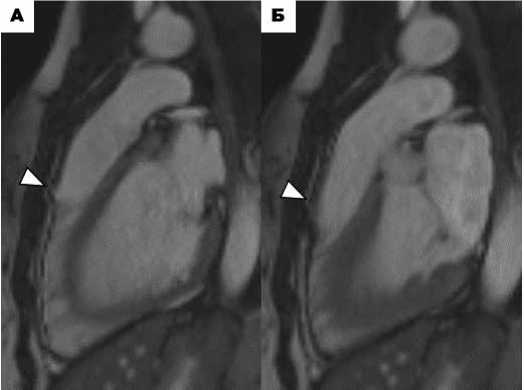

По данным МРТ сердца региональный дискинез был выявлен у всех пациентов. Медиана ФВ ПЖ составила 42,5 [36,0; 53,8]%, систолическая дисфункция ПЖ установлена у 4 (50,0%) пациентов. У 2 пациентов (№ 855, 987) по данным МРТ выявлены дилатация ПЖ (иКДО 111 мл/м 2 и 130 мл/м 2 ) и сохраненная ФВ ПЖ (ФВ ПЖ 56% и 53%) без определяемого отсроченного накопления контрастного вещества (КВ) в миокарде ПЖ (рис. 1).

Рисунок 1. А-Б. МРТ сердца пациента № 855. А. Изображения сердца в четырёхкамерной проекции в конечно-диастолическую фазу (А – кино-изображение, Б - последовательность с отсроченным контрастным усилением). Расширение ПЖ, иКДО 111 мл/м 2 , (тонкие белые стрелки) без определяемого отсроченного накопления КВ в миокарде ПЖ. «Спортивное сердце». В-Г. МРТ сердца пациента № 987. В. Изображения сердца в четырёхкамерной проекции в конечно-диастолическую фазу (В – кино-изображение, Г – последовательность с отсроченным контрастным усилением). Расширение ПЖ, иКДО 130 мл/м 2 , (тонкие белые стрелки) без определяемого отсроченного накопления КВ в миокарде ПЖ. «Спортивное сердце».

Figure 1. А-Б. Cardiac MRI of patient №855. A. Four-chamber end-diastolic cardiac images (A – cine image, Б – delayed contrast-enhanced sequence). RV dilation, iEDV 111 ml/m 2 (thin white arrows) without detectable delayed CF accumulation in the RV myocardium. «Athlete's heart». В-Г. Cardiac MRI of patient №987. C. Four-chamber end-diastolic cardiac images (В – cine image, Г – delayed contrast-enhanced sequence). RV dilation, iEDV 130 ml/m 2 (thin white arrows) without detectable delayed CF accumulation in the RV myocardium. «Athlete's heart».